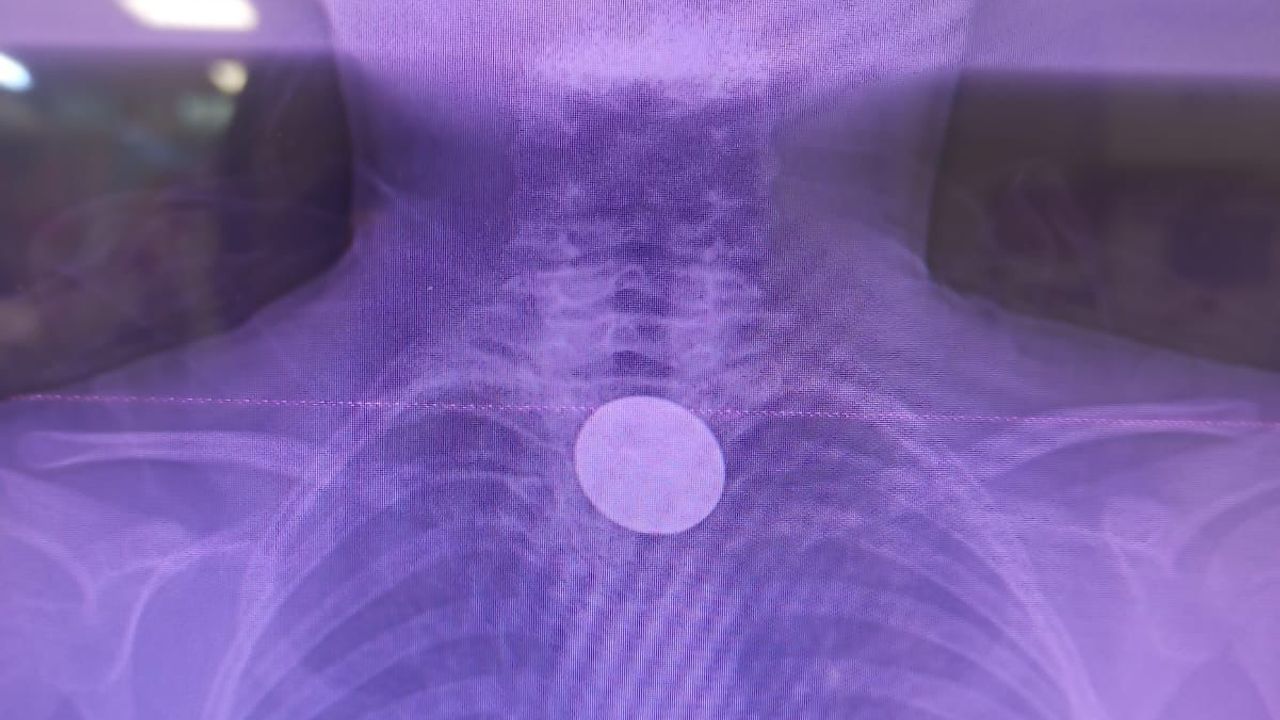

Siirt’te oyun oynadığı sırada boğazına cisim kaçan 8 yaşındaki Y.K., ailesi tarafından panikle Siirt Eğitim ve Araştırma Hastanesi’ne getirildi. Acil serviste yapılan ilk muayene ve çekilen görüntüleme tetkikleri sonucunda, küçük çocuğun madeni para yuttuğu ve paranın yemek borusunda takılı kaldığı tespit edildi.

Doktorların titiz müdahalesi sonucu, Y.K.'nın yemek borusuna kadar ilerleyen madeni 5 lira, cerrahi bir komplikasyon yaşanmadan başarıyla çıkarıldı. Operasyonun ardından bir süre müşahede altında tutulan küçük çocuk, genel sağlık durumunun iyi olması üzerine taburcu edildi.